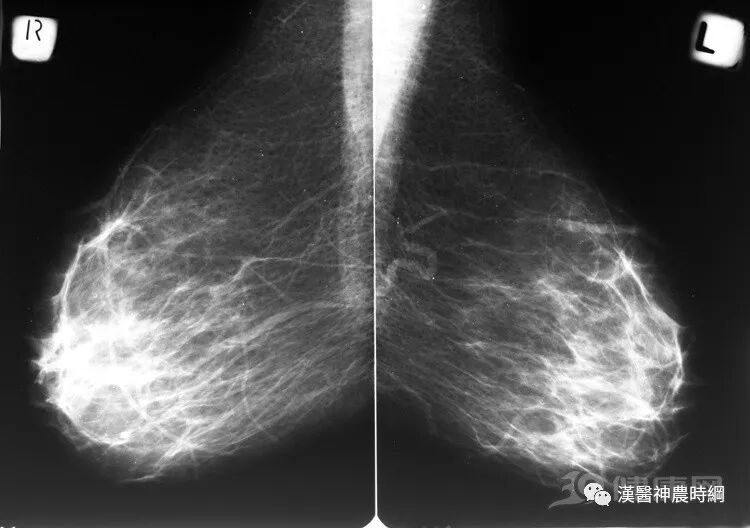

這些情況可能易患乳腺癌?

乳腺癌

哪些女性容易患乳腺癌

乳房赋予了女人特有的美丽及性感,也使女性易患上乳腺癌。但是到底哪些女人容易罹患乳腺癌呢?

(一)35~55岁为乳癌好发年龄

一般认为乳腺癌与卵巢功能、遗传因素、婚育及哺乳等因素有密切关系。因此乳腺癌主要发生于青春期以后的成年妇女,35~55岁为好发年龄,有以下情况就要谨防乳腺癌的发生。